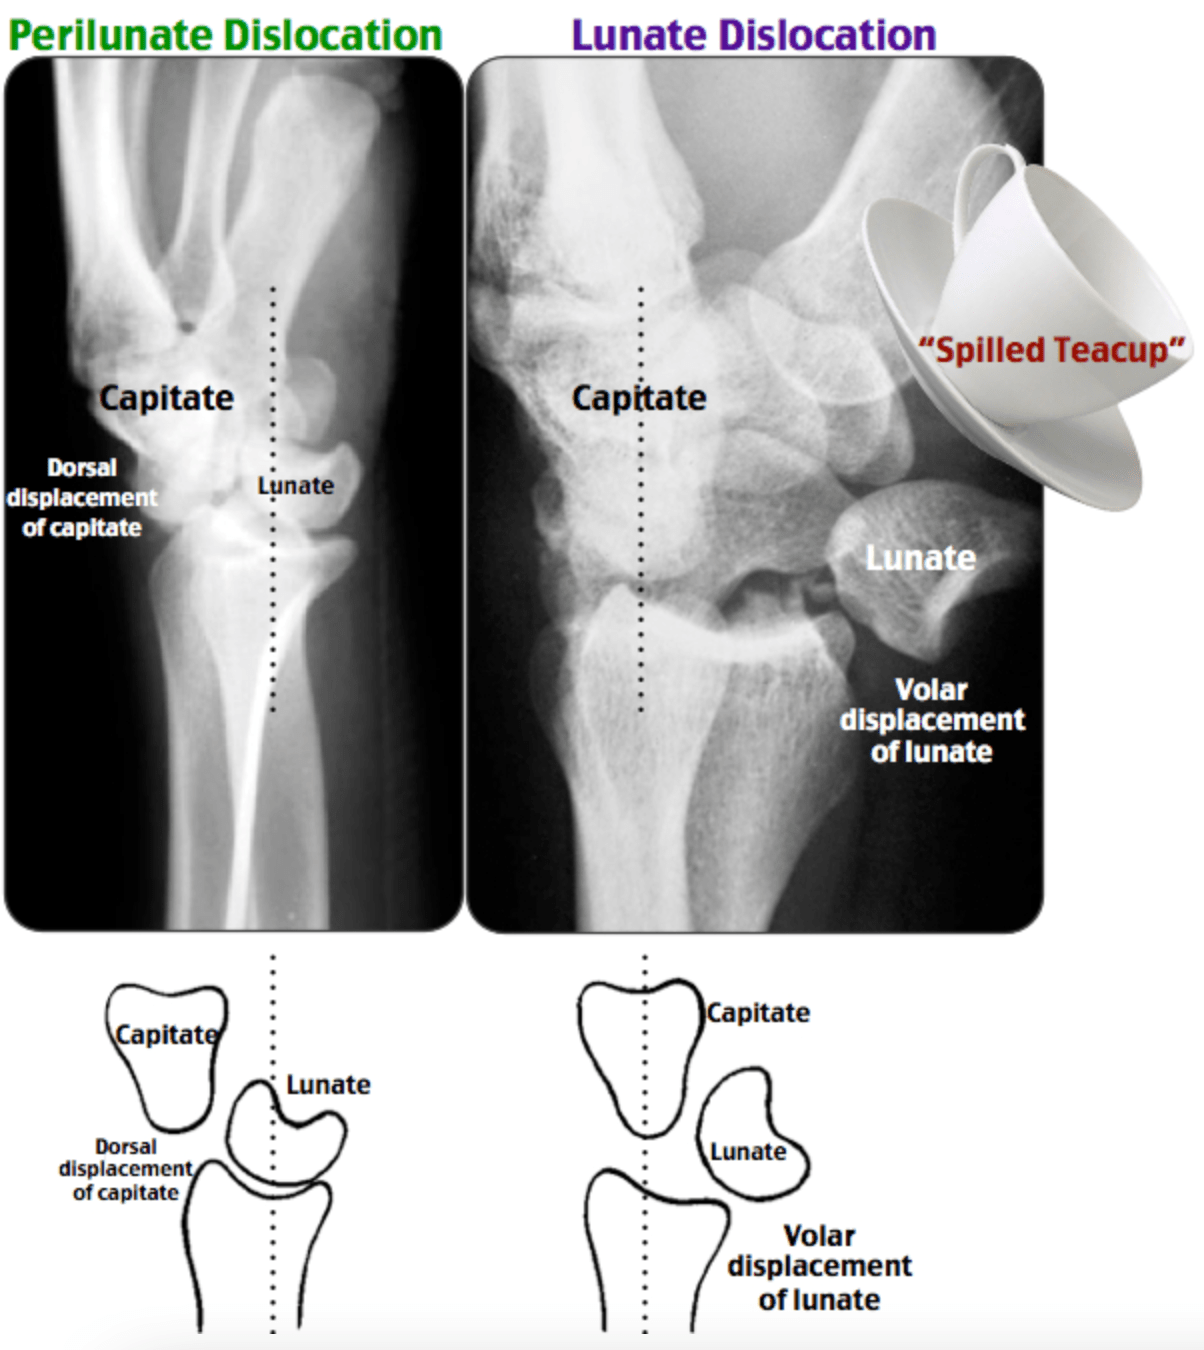

• Radiology

• X-ray of bones and a cupDescription automatically generated